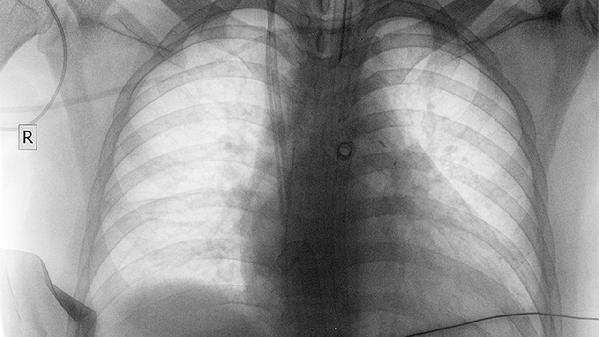

复方斑蝥胶囊含斑蝥素等成分,可通过干扰肿瘤细胞DNA合成抑制其增殖。部分临床观察显示,该药联合化疗可能延缓非小细胞肺癌进展,但单独使用效果有限。用药期间需定期复查影像学评估疗效。